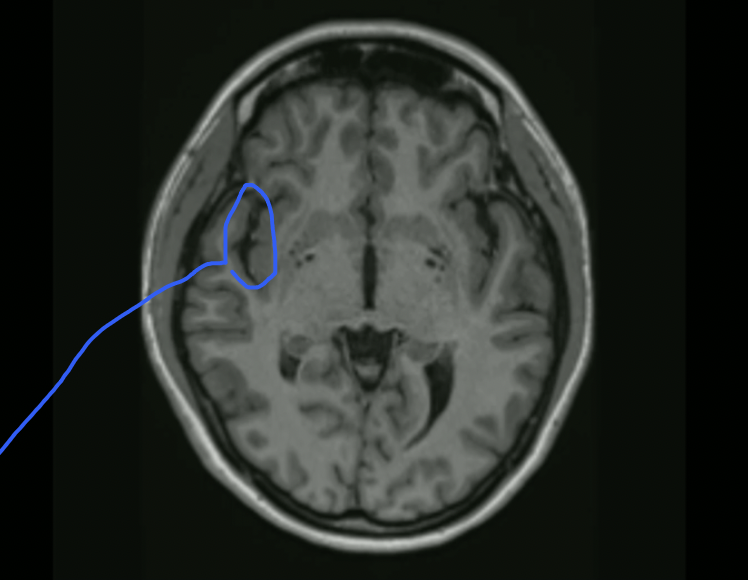

<p>What is this?</p>

What is this?

Basal Nuclei